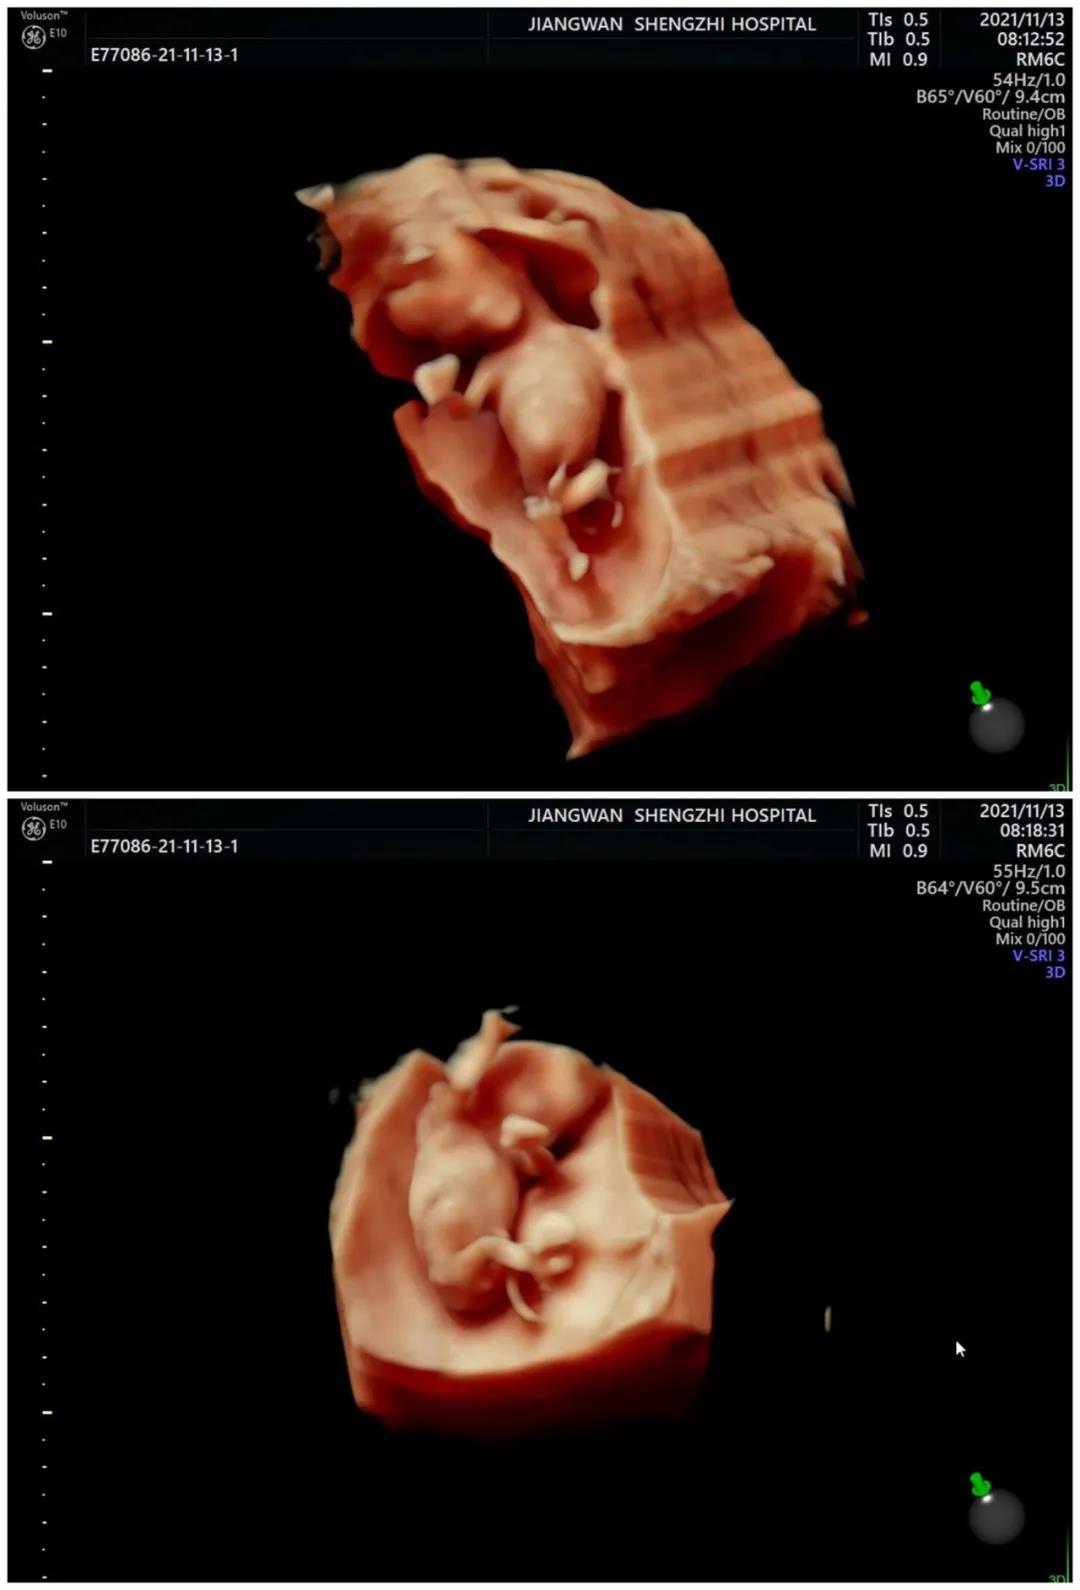

清晰精准的四维彩超影像